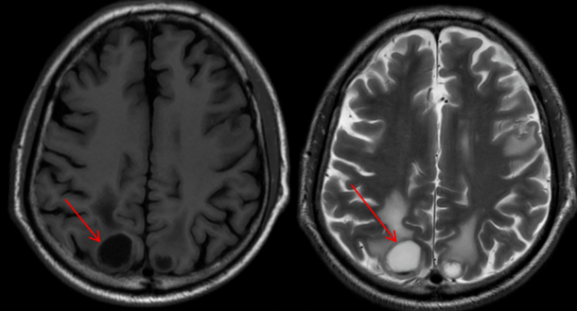

MR表现:颅内见多发大小不等小结节、类环形T1等/低、T2高、T2falir等信号,DWI部分高信号,ADC呈高信号,部分病灶周围环以水肿,增强扫描病灶呈点状、环形强化,较大者位于右侧顶叶,周围水肿未见强化(长箭头)。

李大爷的影像表现——多发、大小不一、环形强化、周围水肿明显——非常符合典型的多发脑转移瘤。